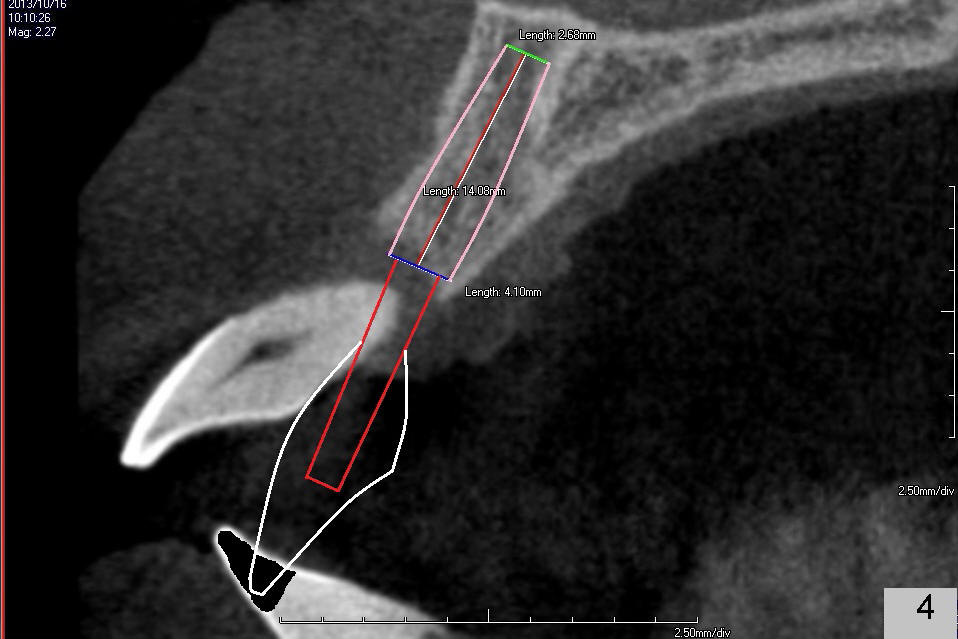

A 49-year-old man has severe chronic periodontitis. The upper central incisors are protrusive and mobile (Fig.1,2: #8,9), but the basal bone is wide and tall (BB in Fig.2). Immediate implants are going to be placed. To avoid malpositioning of the implant, initial osteotomy begins close to the palatal plate (Fig.3: P), while the axis of the osteotomy is parallel to and close to the buccal plate (>). The implant (Fig.4 pink), abutment (red) and the crown (white) will be in a favorable trajectory. To reduce protrusion, the incisal edge of the lower central will be trimmed (compare Fig.3 * and Fig.4 black area).